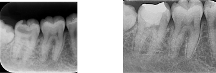

神経の部屋に近接する深い虫歯でしたが、MTAセメントにより神経を保護し、歯の生理的機能を保ったまま修復しました。

歯髄温存療法66,000円+レジン築造33,000円+ゴールドインレー132,000円